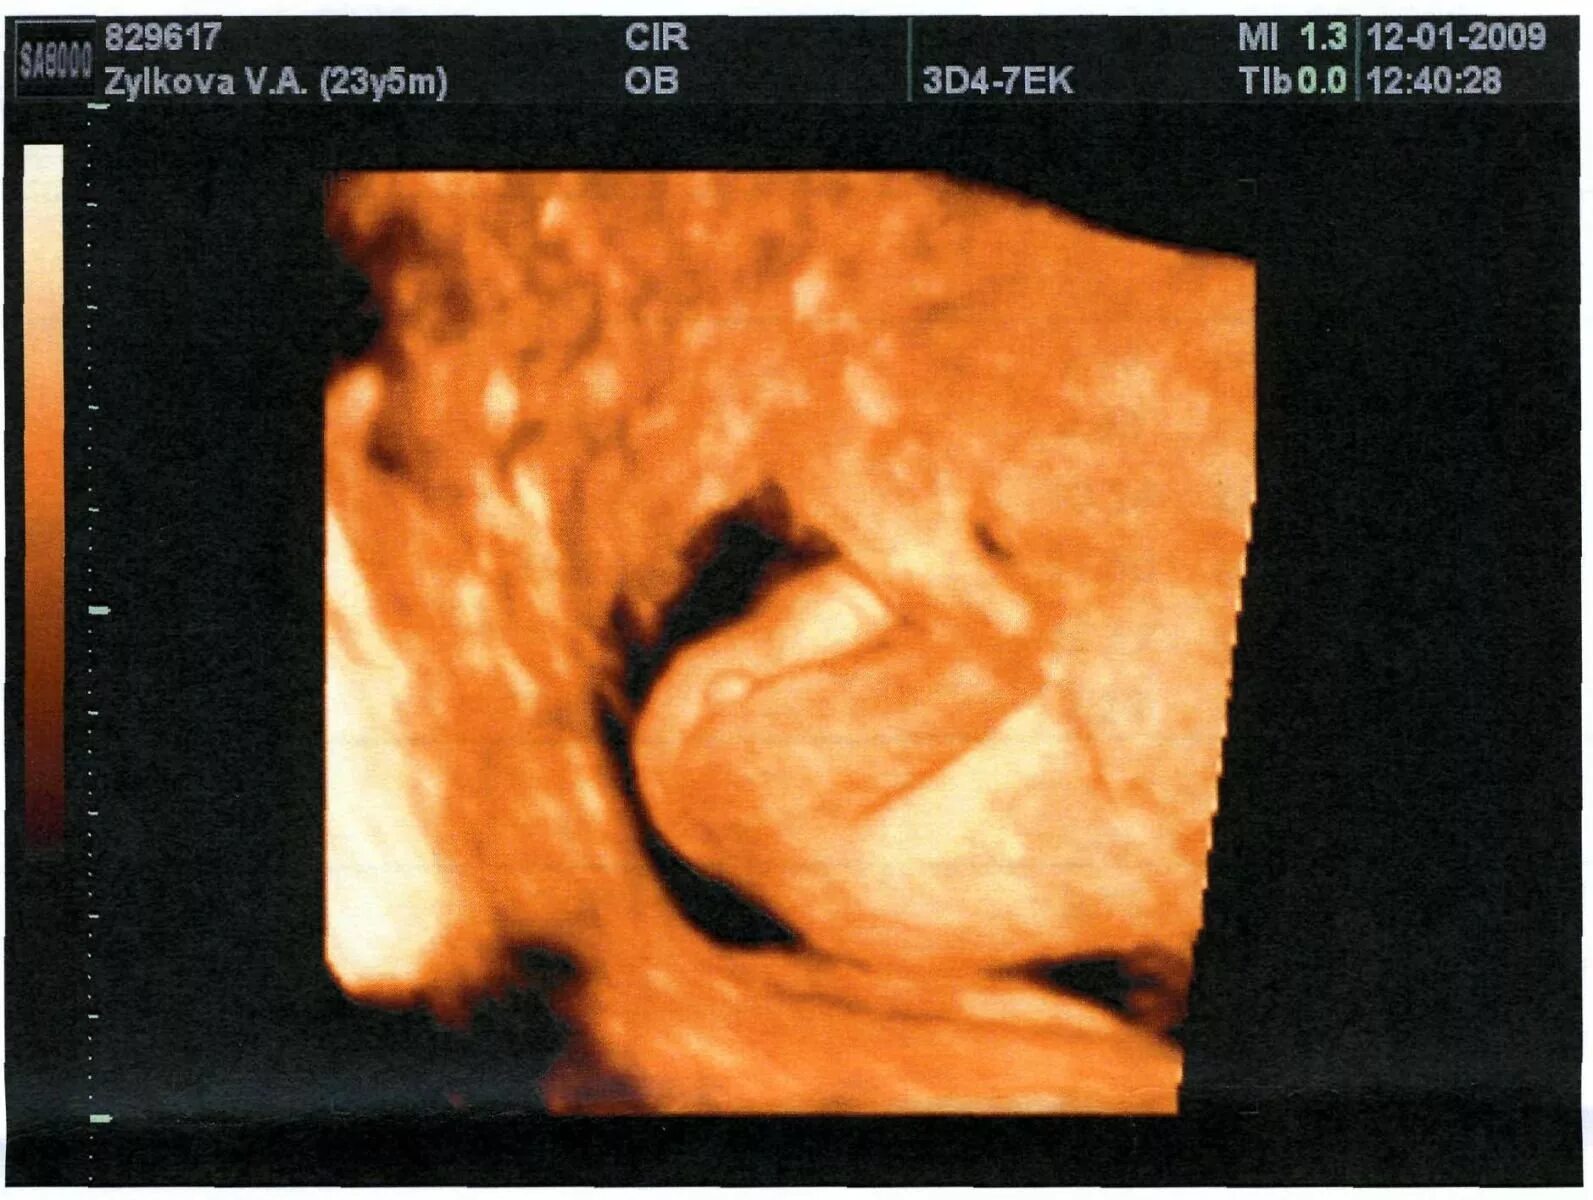

15 неделя можно узнать пол ребенка